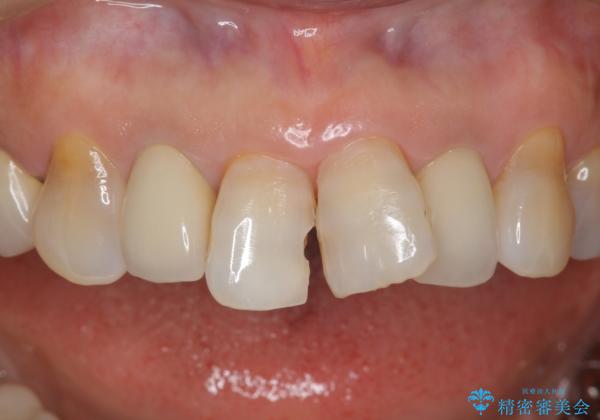

これを機にセラミックでかぶせて、前歯の歯並びも良くしたいとのことでした。

左上の前歯のみねじれが大きいため、歯の位置をひっこめたかぶせものにするために、神経の治療を行っています。

両側の前歯もやり替えをすることで、前歯の前突感も無くしています。